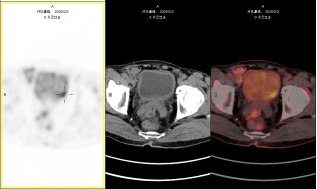

blob.pngblob.png

图注:左图为常规显像、右图为延迟显像,延迟显像明确膀胱壁占位。